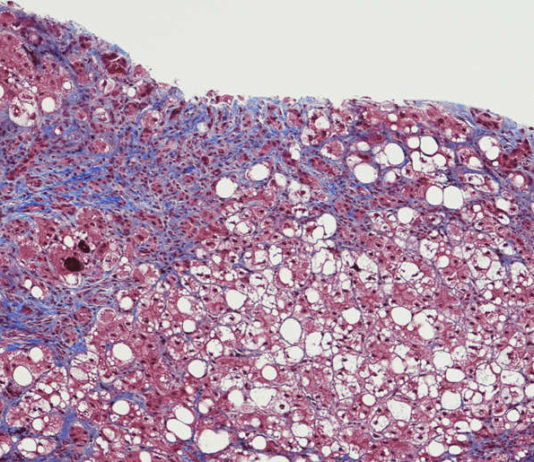

Cientistas do centro de pesquisa e tratamento de câncer City of Hope, nos Estados Unidos, e da empresa de biotecnologia Imugene, na Austrália, acabaram de realizar o primeiro teste humano de uma vacina contra o câncer chamada CF33-hNIS ou Vaxinia.

O tratamento conhecido como terapia de vírus oncolítico consiste em...